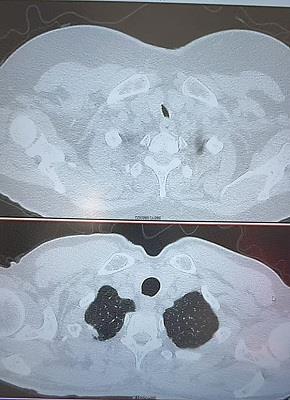

患者系胆囊结石伴胆囊炎入院,既往有车祸伤行开颅手术及气管切开术。体格检查可见颈部有一明显疤痕,CT示:胸锁关节上缘水平气管管腔局限性狭窄。患者平时活动后有气短症状。